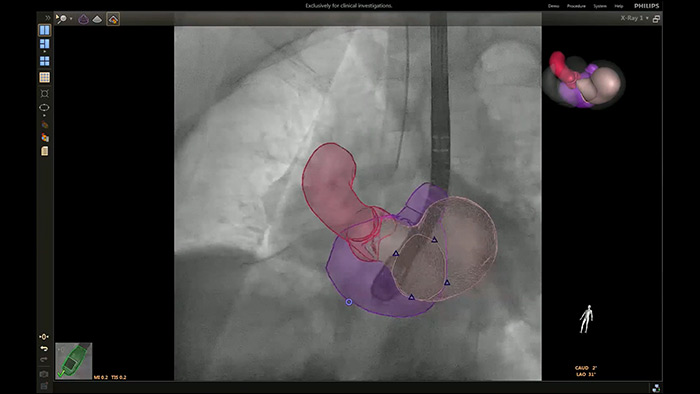

El uso de ProcedureCards, el control de la sala al alcance de la mano con una flexibilidad ilimitada y la generación de la fusión en vivo de los datos de imagen críticos en tiempo real mejora la eficiencia del laboratorio y mejora la confianza en cada paso del tratamiento.

En el centro de nuestra suite, la exclusiva solución EchoNavigator es el ejemplo emblemático del compromiso de Philips con la multimodalidad y la integración del flujo de trabajo, aporta lo mejor de ambos mundos del líder de la industria en soluciones cardíacas intervencionistas de rayos X y ecografía.

Implementación de la superposición de la ETE 3D en vivo de la oclusión de la LAA con EchoNavigator

Guía de punción transeptal mediante EchoNavigator